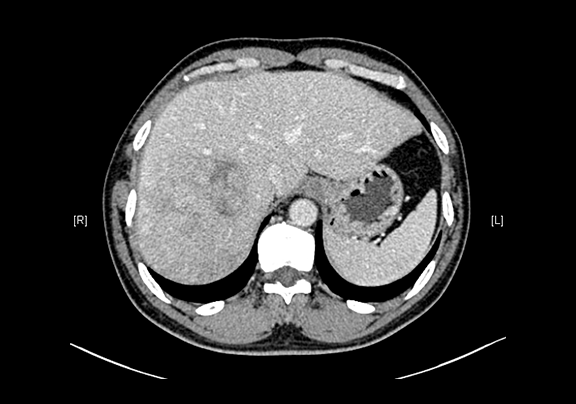

现病史:患者20余天前查体,行腹部超声检查时发现:肝右叶低回声结节,大小约5.8*4.7cm,无腹痛、腹胀,无腰背部放散痛、皮肤巩膜无黄染,无寒战、高热,无咳嗽、咳痰、胸闷、气短,无恶心、呕吐,无腹泻、血便,无尿频、尿急、尿痛、血尿。上腹部动态三维成像(增强)CT检查示,肝右后叶上段占位性病变,肿瘤性病变。

下腹部增强CT示:肝右后叶上段占位性病变,肿瘤性病变,考虑肝癌合并出血可能性大,肝多发小囊肿

术前CT检查:

动脉期

静脉期

平衡期